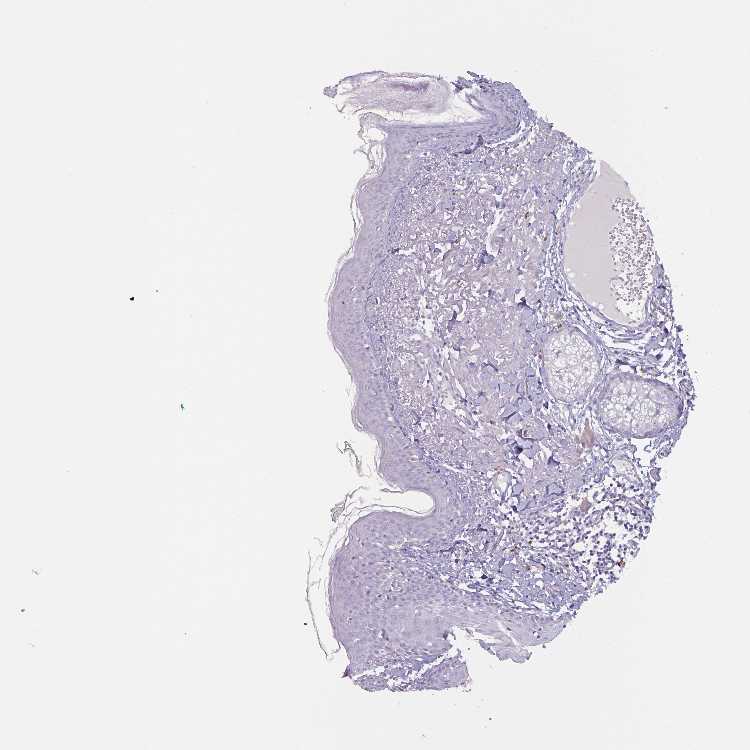

SKIN 1 - Antibody stainingi

Antibody staining in the annotated cell types in the current human tissue is reported as not detected, low, medium, or high, based on conventional immunohistochemistry profiling in selected tissues. This score is based on the combination of the staining intensity and fraction of stained cells.

Each image is clickable and will lead to virtual microscopy that enables deeper exploration of all samples and also displays staining intensity scores, fraction scores and subcellular localization as well as patient and tissue information for each sample.

Antibody HPA052809

Langerhans Not detected

Fibroblasts Not detected

Keratinocytes Not detected

Melanocytes Not detected

SKIN 2 - Antibody stainingi

Epidermal cells Low